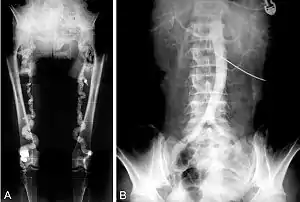

![]() Ренгенографічне зображення вираженого кальцинозу низхідного відділу аорти та стегнових артерій Ренгенографічне зображення вираженого кальцинозу низхідного відділу аорти та стегнових артерій | |